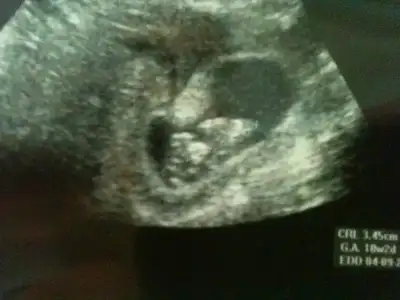

Aranıza yeni katıldık. Bu konu çok ilgimizi çekti. Fotoyu ekliyoruz. Acaba yardım edebilir misiniz? Sizce bebeğimiz kız mı yoksa erkek mi? Bebeğimiz 10 hafta 2 günlük..Çok teşekkürler...

$IMG_1299.webp $IMG_1300.webp $IMG_1299.webp $IMG_1300.webp

Ilk.kez kendimden emim bi sekilde erkek diyorum ama tabii dr daha iyi bilir :))) ogrenince hbr verirsen sevinirim bacim

Fatos nasil emin olsun kiz nubu pasparalel gelgelelim buyuk yani haftasida kucuk yani kiz gibi gorunuyor ama erkege donecek bi nub gibi az daha buyumeli ama sonuc olarak bende erkek diyore

Valla ben de bi bakıyorum erkek gibi, bi bakıyorum kız gibi geliyo hiç emin olamadım :) doktor da ben ısrar edince erkeğe benzettim bi an ama daha cok erken, yanilma ihtimalim fazla, 2 hafta sonra tekrar bakalım dedi.